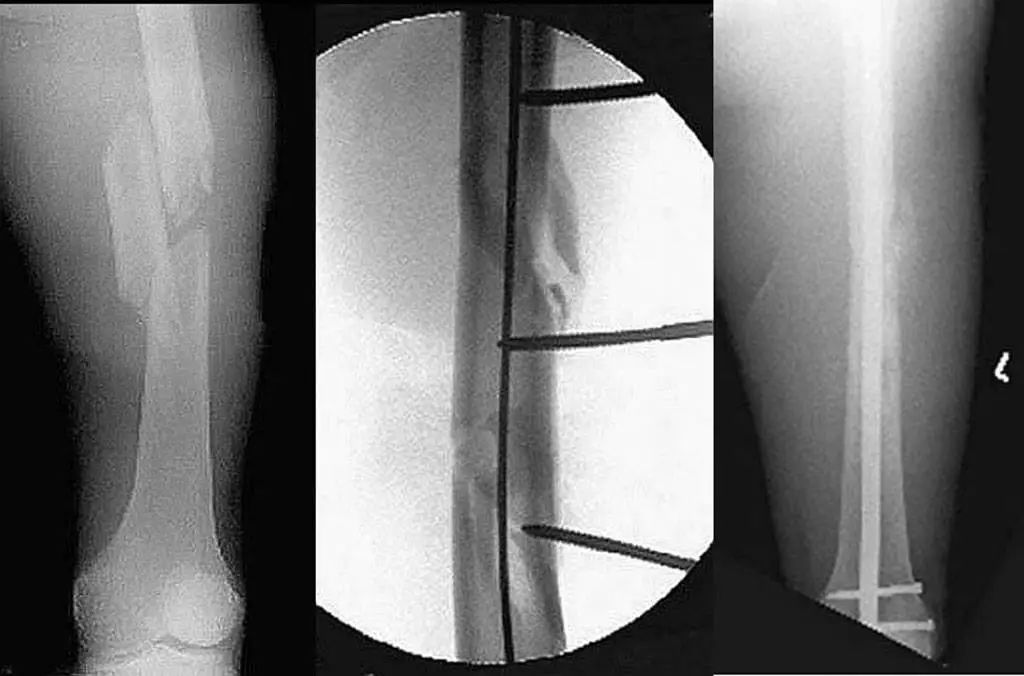

Diagnostic radiographique : L'évaluation standard de l'imagerie de la cheville doit comprendre 3 phases : antéropostérieure (Figure 8), point de cheville (15 ° de rotation interne) (Figure 9) et latérale (Figure 10).

Lorsque l'articulation de la cheville est gravement blessée, la cheville interne et externe et le talus seront déplacés à 11 degrés différents (Figure 11).Les radiographies statiques ne reflètent pas avec précision la stabilité de l'articulation de la cheville.Les radiographies de stress et l'IRM peuvent améliorer l'évaluation de la stabilité de l'articulation de la cheville et des lésions ligamentaires (Figure 12).

Dans ce cas, le type de blessure à la cheville doit être déterminé avec précision par le mécanisme de la blessure et les données radiologiques du membre affecté afin de guider correctement le repositionnement et la fixation.

Parfois, une simple fracture médiale de la cheville peut faire partie d'une 'fracture de Maisonneuve' plus complexe, qui comprend également une fracture du péroné proximal et une lésion ligamentaire combinée, de sorte que l'ensemble du tibiofibula doit être examiné par radiographie.

Figure 8 Position avant et arrière

Figure 9 Points de cheville (15° de rotation interne)

Figure 10 Position latérale

Figure 11 Déplacement de la fracture apparemment combiné à une luxation

Figure 12 Radiographie de stress (rupture du ligament triangulaire)